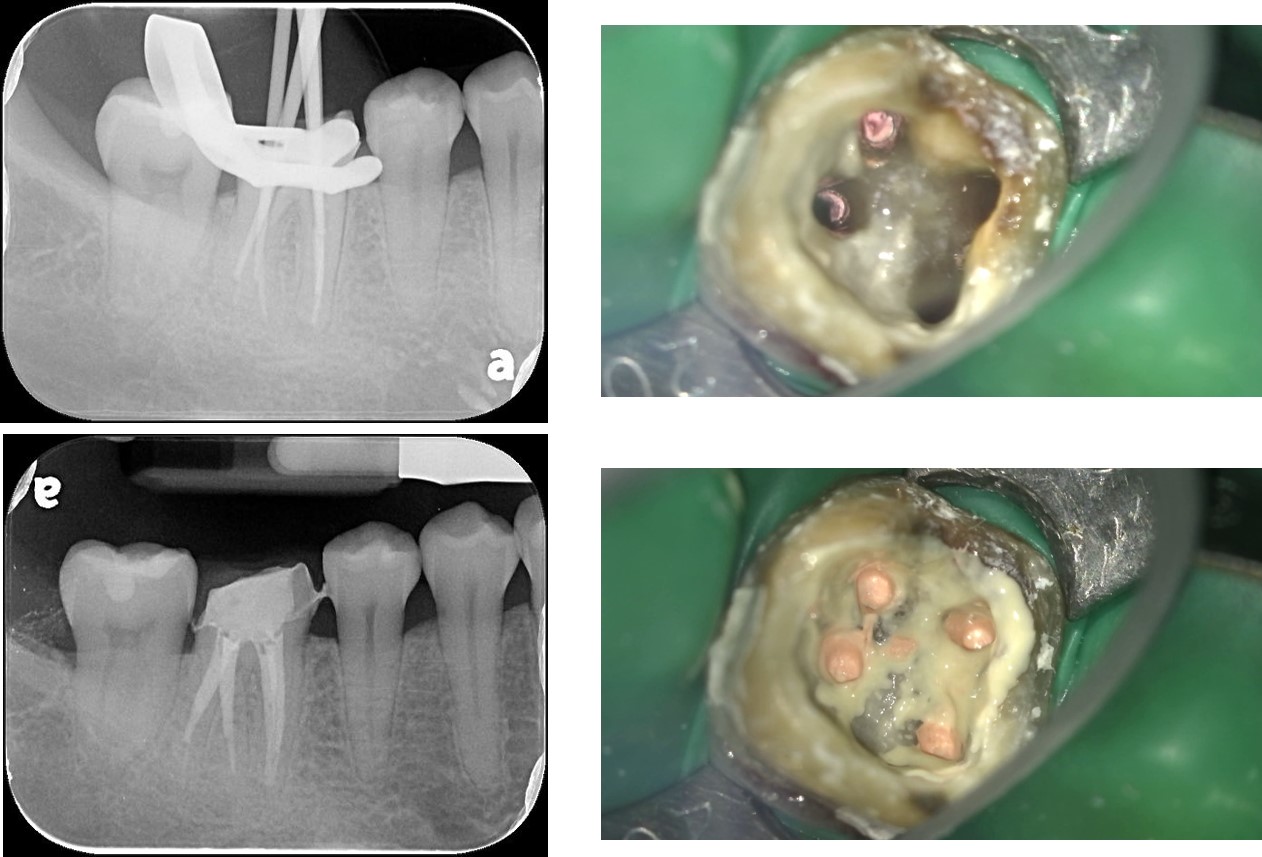

顯微根管治療

鑄造金屬釘柱